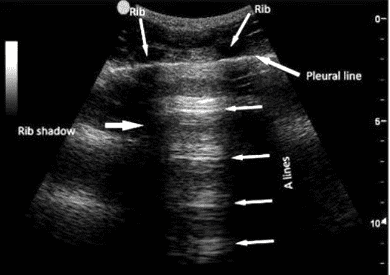

- A-lines: Horizontal, evenly spaced lines that indicate normal, air-filled lungs.

Figure 1. Normal lung (A-lines): Parallel, equidistant, horizontal lines below pleural line. Note the location of the pleural line, ribs, rib shadows. Observe how the A-lines tend to fade away (less echogenic and even less clear) as they appear further away from the transducer footprint. In contrast, B-lines extend to the bottom of the screen without fading or losing intensity (See Figure 2).